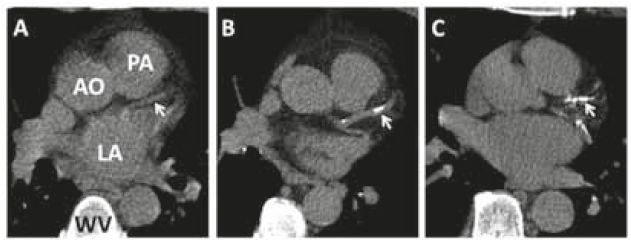

CT-calciumscore: geschikte test voor uitsluiting coronairlijden

De CT-calciumscore is een relatief recente tweedelijnstechniek voor de analyse van coronairlijden. Het onderzoek is vanwege de hoge negatief voorspellende waarde uitermate geschikt voor het uitsluiten van gecalcificeerd coronairlijden bij patiënten met een atypisch klachtenpatroon. Bij…